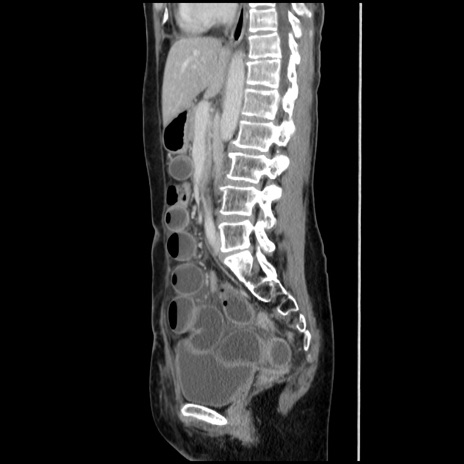

症例32(矢状断像)

横断像